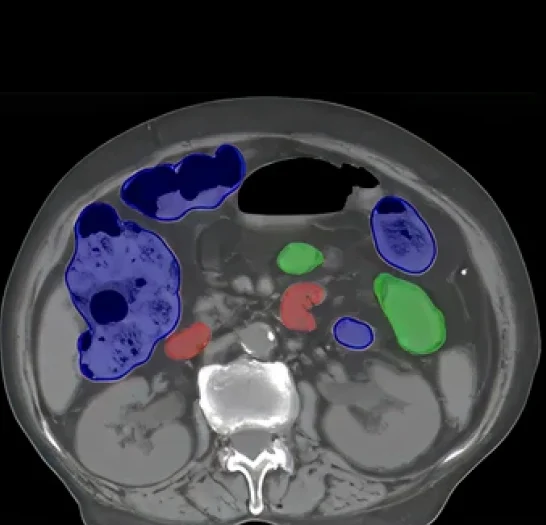

Gastroenterology CT Annotation & Segmentation

Pareidolia Systems offers gastroenterology CT annotation and segmentation services that power imaging data-driven AI diagnostics. Our experts label gastrointestinal organs, lesions, and tumors with precision to enhance disease detection and treatment planning. Each dataset undergoes multi-level validation, ensuring accurate, consistent, and clinically reliable AI-ready medical imaging data.